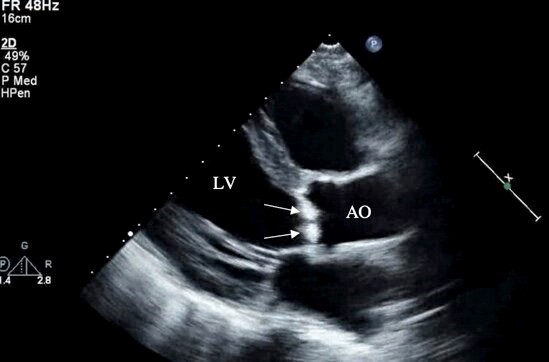

NBTE vegetations are most frequently left sided, with two-thirds involving the mitral valve and the remainder occurring on the aortic valve. Rarely, both valves can be affected [5, 8, 9, 38]. Due to the small size of the many vegetations seen in NBTE, pathology may frequently escape detection by TTE. In patients in whom there is a high suspicion of NBTE in the setting of an unclear TTE scan, a TEE is indicated [23] (Fig. 2). It has been reported that cardiac MRI may be useful to evaluate valvular vegetations in NBTE [39].

Fig. 2.Transthoracic echocardiography (parasternal long axis view) of a patient with nonbacterial thrombotic endocarditis showing large irregular hyperechoic lesions consistent with vegetations on the aortic valve (arrows). LV, left ventricle; AO, ascending aorta.